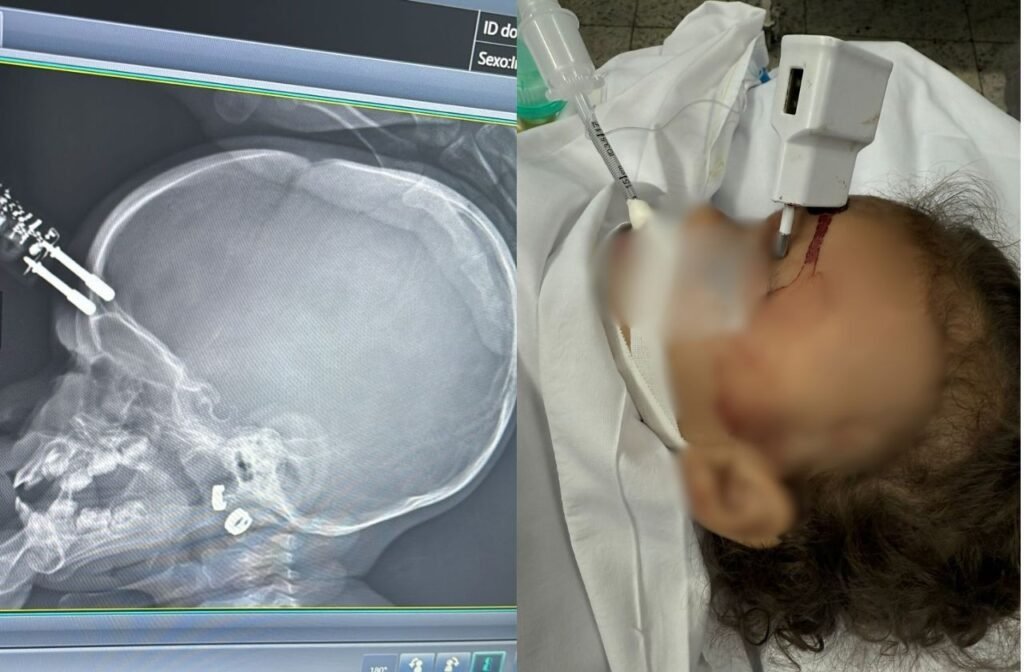

Uma menina de 1 ano e quatro meses sofreu um grave acidente doméstico em Divinópolis, na região oeste de Minas Gerais, ao cair da cama e atingir a testa em um carregador de celular que estava no chão.

O objeto ficou cravado na cabeça da criança, que precisou ser submetida a cirurgia de emergência.

O acidente ocorreu na noite de segunda-feira (12). De acordo com a mãe, ela foi ao banheiro e deixou a filha sozinha na cama por alguns instantes. Logo depois, ouviu o choro da menina e a encontrou no chão, com os pinos do carregador cravados na testa.

Ela acionou o Samu, que realizou o atendimento e encaminhou as duas para a UPA. Segundo o neurologista Bruno Castro, que atendeu o caso, o carregador chegou a perfurar o crânio da menina, provocando uma fratura.

Ela foi inicialmente atendida na Unidade de Pronto Atendimento (UPA) de Divinópolis e, em seguida, transferida para o Hospital São João de Deus, onde passou por cirurgia imediata para retirada do objeto, correção da lesão e contenção de um pequeno sangramento.